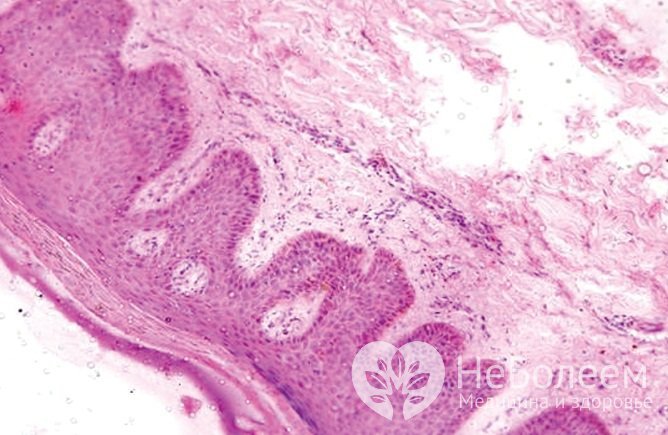

Лишай – это большая группа кожных заболеваний различного происхождения, которые характеризуются появлением на коже пятен, папул или узелковых элементов, как правило, сопровождающихся шелушением, а также нарушением пигментации.

Красный плоский лишай дебютирует появлением папул розовато-фиолетового цвета с блестящей поверхностью. Элементы сыпи локализуются на туловище, конечностях, слизистых оболочках полости рта и наружных половых органов, их появление может сопровождаться зудом и болезненностью. В ряде случаев поражение слизистых оболочек возникает изолированно.